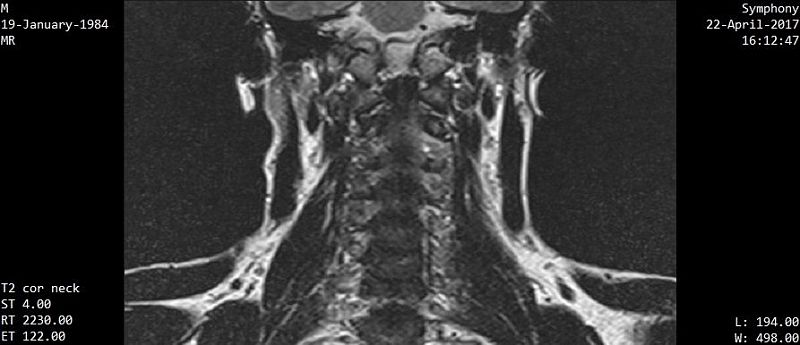

На снимках МРТ стрелками обозначен смещённый первый шейный позвонок (изображение слева); светлые пятна (на изображении справа) обозначают боковые массы атланта; асимметрия говорит о том, что позвонок повёрнут